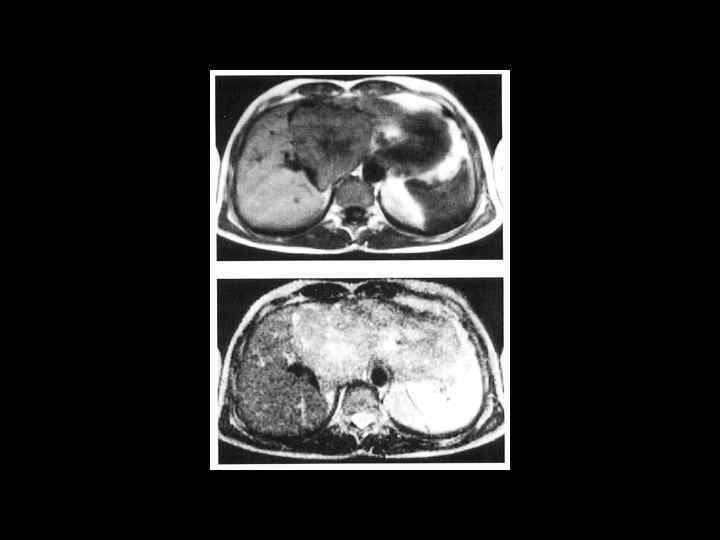

АКТУАЛЬНЫЕ ВОПРОСЫ РЕНТГЕНОЛОГИИ ЛУЧЕВАЯ ДИАГНОСТИКА ОЧАГОВЫХ ПОРАЖЕНИЙ ПЕЧЕНИ Кавернозная гемангиома печени МР- семиотика: - образование с гиперинтенсивным сигналом на Т-2 взвешенном изображении -после введения контрастного вещества- динамика изменений такая же, как при КТ

Клиническое наблюдение. Пациентка К, 1966 г. р.

Та же пациентка